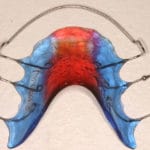

Pour les enfants et les jeunes plutôt des appareils amovibles, ainsi que des appareils fixes collés (pièces métalliques) pour aligner les dents. Ceux-ci peuvent être choisis en option transparentes.